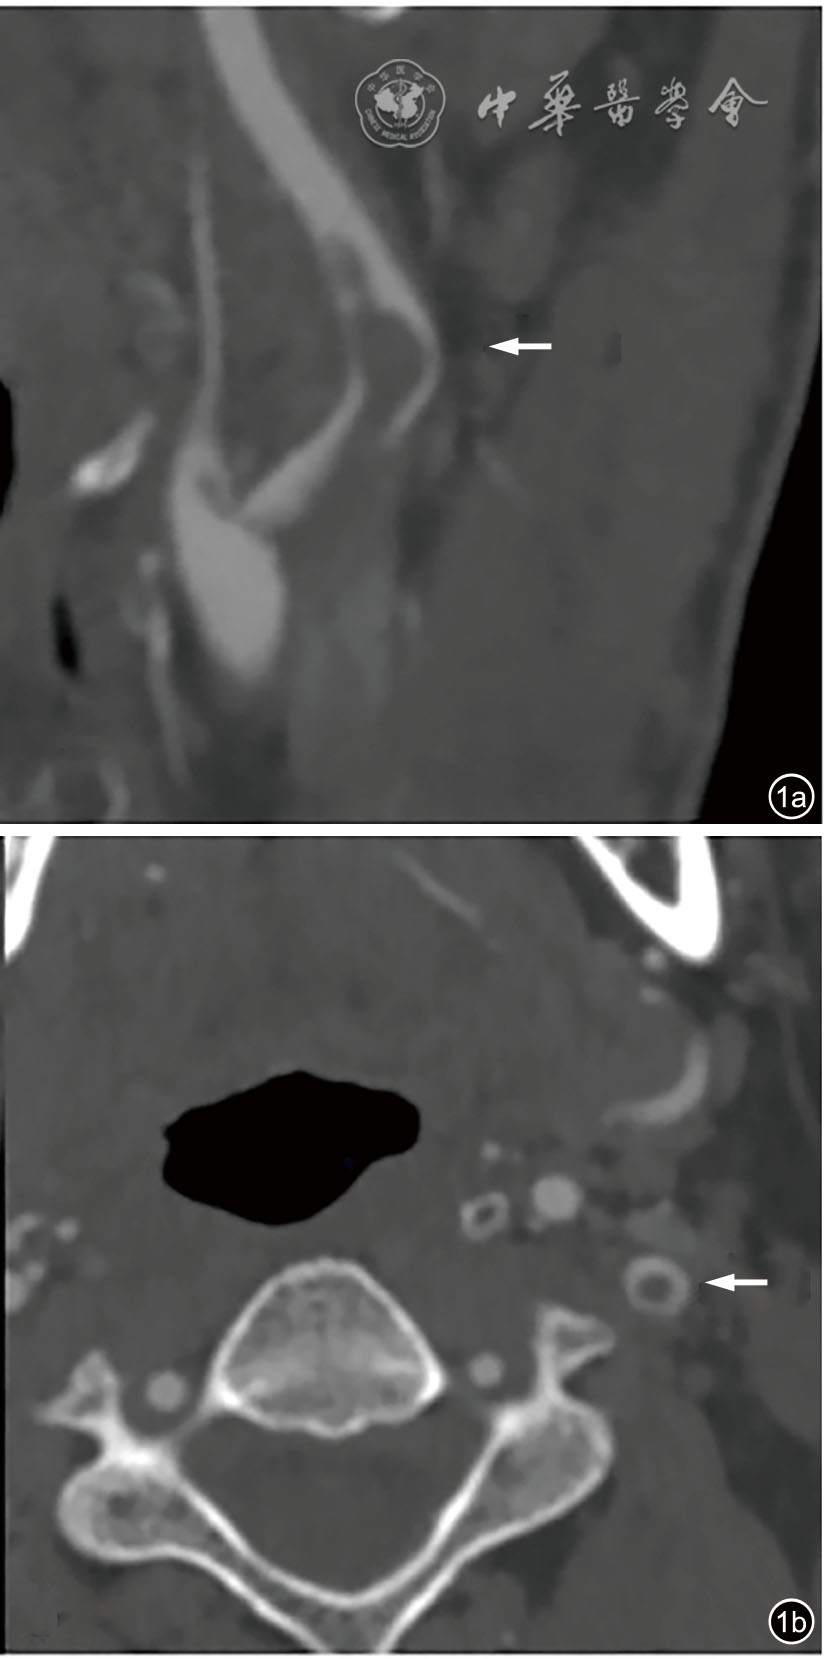

图1 颈动脉漂浮血栓的CT血管成像的影像学表现。图a为矢状位图,表现为血管腔内充盈缺损(白色箭头);图b为横轴位图,“甜甜圈征”(白色箭头)[4]